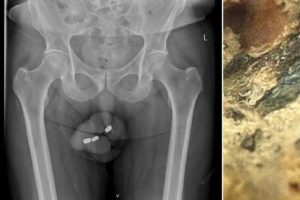

Sharing eye-watering details of the incident in a medical journal, doctors told how unsuccessful attempts to fish out the 1.3cm-wide batteries only saw them pushed deeper down his urethra.

Doctors examining the man found that the opening of his urethra was stained black, while surgery later revealed necrosis had occurred.

Each of the batteries were coated with a ‘black tar-like material’ and the man’s urethra had suffered ‘extensive’ burns, they wrote.